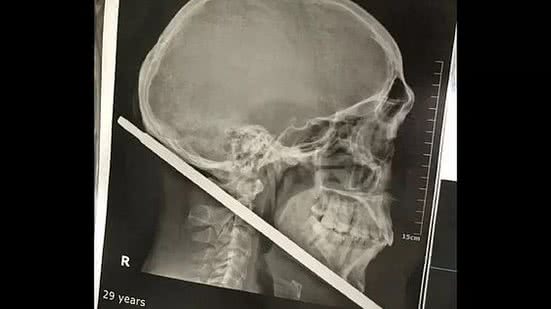

Aldinailson Pereira da Silva, de 29 anos, viveu momentos de terror na segunda-feira (20), em Monte Alegre (PA), ao sofrer um acidente com "bufete", arma caseira com ferro semelhante a uma espingarda. O ferro atravessou a região entre o pescoço e o crânio do homem e por menos de 1 centímetro não atingiu a carótida interna, artéria que irriga o cérebro. "Eu sou um milagre", disse ele após o susto.

"Ele é um milagre, foi questão de menos de 1 centímetro a distância da carótida interna, que é uma grande artéria que irriga o cérebro, se houvesse lesão nessa arterial ele morreria e não teria nem chance", afirmou o cirurgião geral Vinicius Savino.

O médico explica ainda que o ferro transfixou a região inframandibular, fixando-se atrás do pavilhão auricular direito e fez um edema local.

Os especialistas avaliaram que não havia comprometimento dos grandes vasos, entre elas, a artéria jugular, artéria carótida interna, externa, veia jugular interna e externa e por esse motivo, a cirurgia foi um sucesso.

Adinailson passou por cirurgia e não ficou com sequelas. Nas mãos dele, o objeto que atravessou seu pescoço e crânio (Foto: HSM / Prefeitura de Santarém / Divulgação)